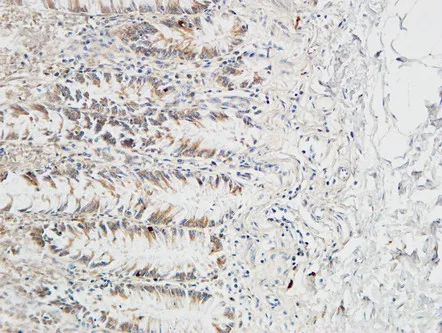

IL-17D Rabbit Polyclonal Antibody

Cat: APRab12507